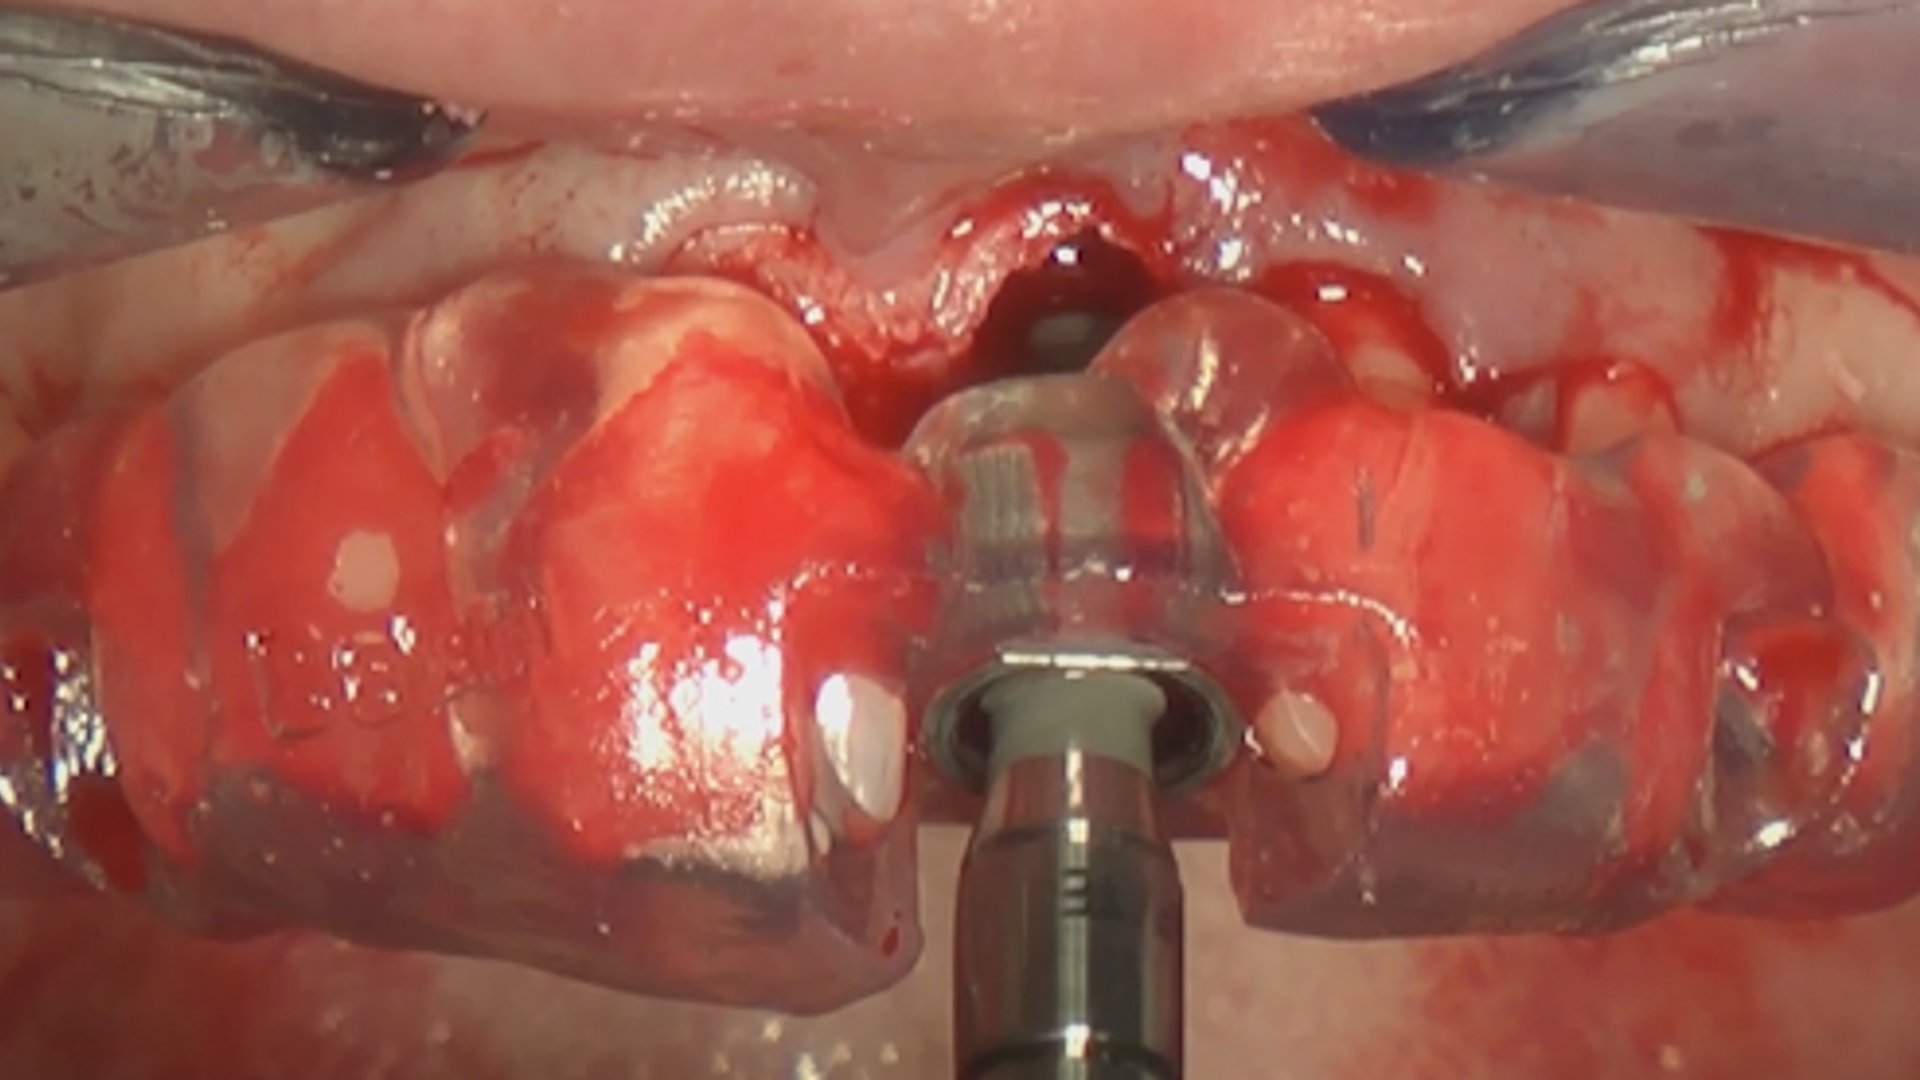

Mucogingival approach to immediate implant placement (Part 1)

Mucogingival approach to immediate implant placement (Part 2)

Mucogingival approach to immediate implant placement in problematic clinical cases